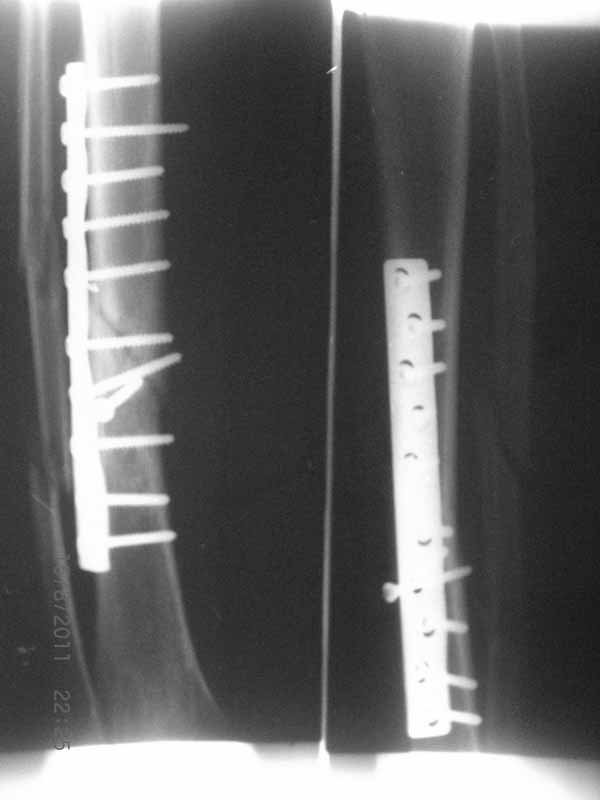

Да уж! Ни один из 3-х оперативных методов предшествующего лечения не был исполнен правильно. Везде был серьезный брак. Хотя любой из методов вполне мог бы и должен был бы привести к сращению,...если бы, да кабы.. В результате имеем то, что имеем. Что делать? Во-первых - подумать. Во-вторых - еще раз подумать. В третьих - еще больше подумать.

Иван, Вам видится зона перелома мертвой, а мне вовсе нет. Есть ли возможность сделать сцинтиграфию с технецием? Это может доказать нежизнеспособность или воспаление концов. Тогда есть резон для такой "крайней" меры как резекция. Есть ли клинические признаки инфекции в области первичной раны?, п\операционных рубцов?, в местах проведения спиц (нет ли спицевого остеомиелита)?.. В общем, вопросов может быть много.

Если нет данных за инфекцию в зоне перелома мы бы аппараптом дозированно устранили деформацию и, не удаляя дистальный фрагмент сломанного гвоздя, закрыто, после рассверливания заштифтовали бы достаточно толстым и надлежащей длины гвоздем.... Если есть спицевой остеомиелит, то также сначала аппарат, затем рассверливанме и цементный спейсор с а\б согласно посевам, через 2-3 недели удалить спейсор, повторно рассверлить и заштифтовать штифтом, возможно покрытым антибиотиком. А если Вы умело владеете техникой Илизарова, и больной согласен, можете оставить аппарат как окончательный метод фиксации....

В любом случае, если нет инфекции в зоне несращения и кость жизнеспособна, упаси Вас Бог что либо открывать и добавлять свободную костную пластику. Надо попытаться все сделать закрыто. Если откроете, то через пару месяцев, а может и раньше, все закончится резекцией и значительно большей чем 4 см...

(АС) Если нет данных за инфекцию в зоне перелома мы бы аппараптом дозированно устранили деформацию и, не удаляя дистальный фрагмент сломанного гвоздя,

(АЧ) Боюсь, кусок гвоздя в канале будет сильно мешать, так что мы бы открыли бы над ним передне-медиальную кожно-надкостнично-костную "крышку", и убрали. То есть не скелетировать чтобы кость даже вдали от несращения.

Подвинуть новый гвоздь обломок сможет, а вот блокировать может не дать. Мы и отломок гвоздя попробовали бы удалить закрыто.